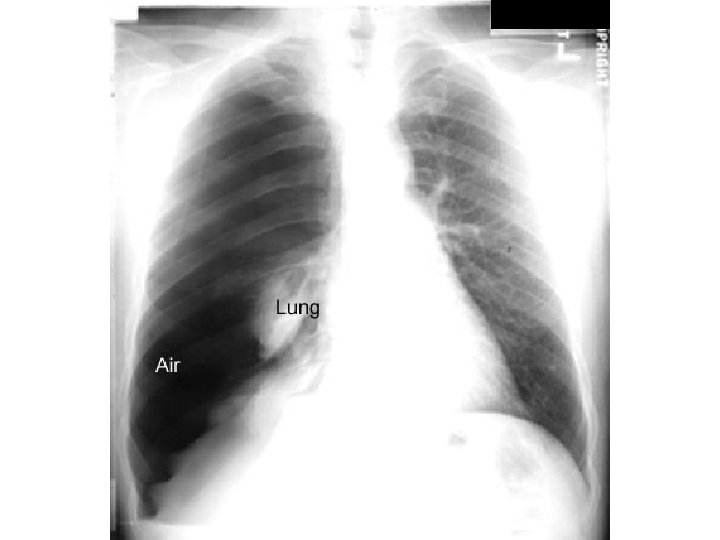

Pneumothorax

Air in pleura Atelectatic lung Hemithorax Mediastinual shift Pneumothorax